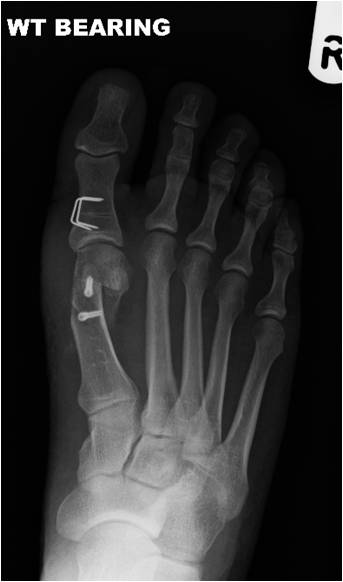

Symptoms include pain in the bump area with or without shoes and occasionally associated discomfort in the ball of the foot (metatarsalgia) and/or lesser toe deformities (Fig 2) such as a hammertoe from direct pressure of the big toe. The diagnosis is confirmed by clinical assessment and x-rays (Fig 3).

Several surgical techniques are available and Mr Weitzel will advise the patient of the most appropriate for her/his individual problem. This will often include a form of osteotomy (cutting and realigning of bone Fig 4) which is then fixed with internal implants such as screws and/or staples.